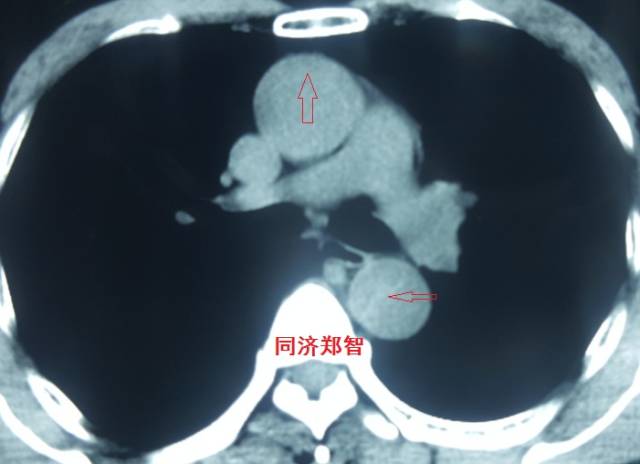

病例九

平扫CT提示降主动脉内膜片征,同时内膜片中可见一钙化点。CTA证实为B型主动脉夹层。